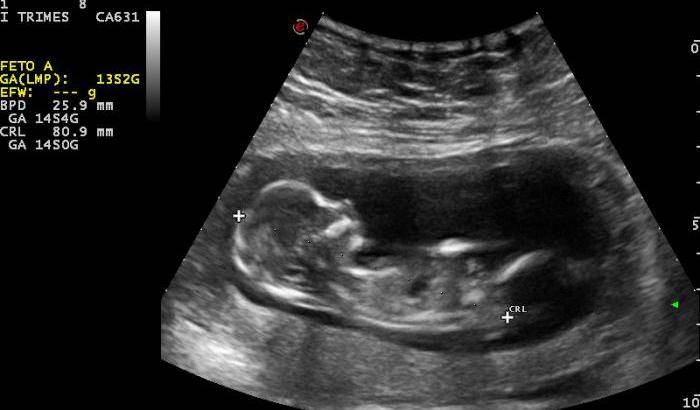

I medici avevano quindi scoperto che la fuoriuscita di sangue poteva dipendere solo da un aborto o da un parto prematuro. In quel momento i sanitari hanno trasmesso il referto alle forze dell’ordine.

Gli agenti del distretto del Casilino, quando sono entrati in casa della coppia, hanno trovato il feto, di quattro mesi e lungo circa 30 centimetri, congelato nel freezer.